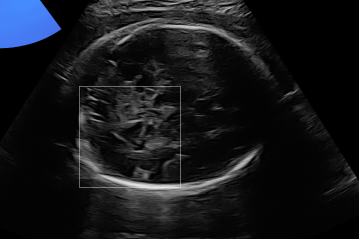

Three in vivo Bmode fetal images with and without aberration correction are presented in Figs. 10-12. GIF images of examples A-L (see Fig. 9 and Table 5) alternating between the corrected and uncorrected images are uploaded as supplementary material. The differences in image quality are easier to appreciate in the GIFs than in a side-by-side comparison. The data points for the three examples are colored black in Fig. 9. Table 5 give tabular values for the global sound speed estimate, sharpness increase (κ𝜅\kappa) and answers from the clinical evaluations.

Refer to caption

(a) Uncorrected Bmode.

(b) Aberration corrected Bmode.

(c) Uncorrected Bmode.

(d) Corrected Bmode.

Figure 10: Example A. In vivo fetal Bmode image using constant 1540 m/stimes1540dividemetersecond1540\text{\,}\mathrm{m}\text{/}\mathrm{s} and the estimated average sound speed map. The average sound speed map is shown in the top right corner and the rightmost colorbar indicates the sound speed values. Alternating GIFs are found in the supplementary material.

The in vivo examples A-C, in Figs. 10-12 respectively, show different nuances of how sound speed aberration correction improves focusing quality. A noticeable improvement in Fig. 10 is the improved contrast and clarity of borders. The sound speed correction seems to remove the double structure indicated by the arrows in Figs. 10c-10d. The skull border and the brain structures in Fig. 11 are also better defined and clearer after aberration correction. Example C in Fig. 12 is the image with the highest increase in Tenengrad κ𝜅\kappa, seen from Fig. 9 and Table 5. The improvement in image quality is evident around the boundary of the fetus body and the correction sharpens the structures indicated by the arrows. The improved contrast between the layers in the shallow tissue layers is also noticeable.